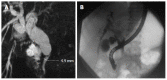

Cystic hepatic neoplasms are rare tumors, and are classified into two separate entities: mucinous cystic neoplasms (MCNs) and intraductal papillary mucinous neoplasms of the bile duct (IPMN-B). We report the case of a 56-year-old woman who presented with abdominal pain and jaundice due to the presence of a large hepatic multilocular cystic tumor associated with an intraductal tumor. Partial hepatectomy with resection of extrahepatic bile ducts demonstrated an intrahepatic MCN and an intraductal IPMN-B. This is the first report of the simultaneous occurrence of these two histologically distinct entities in the liver.